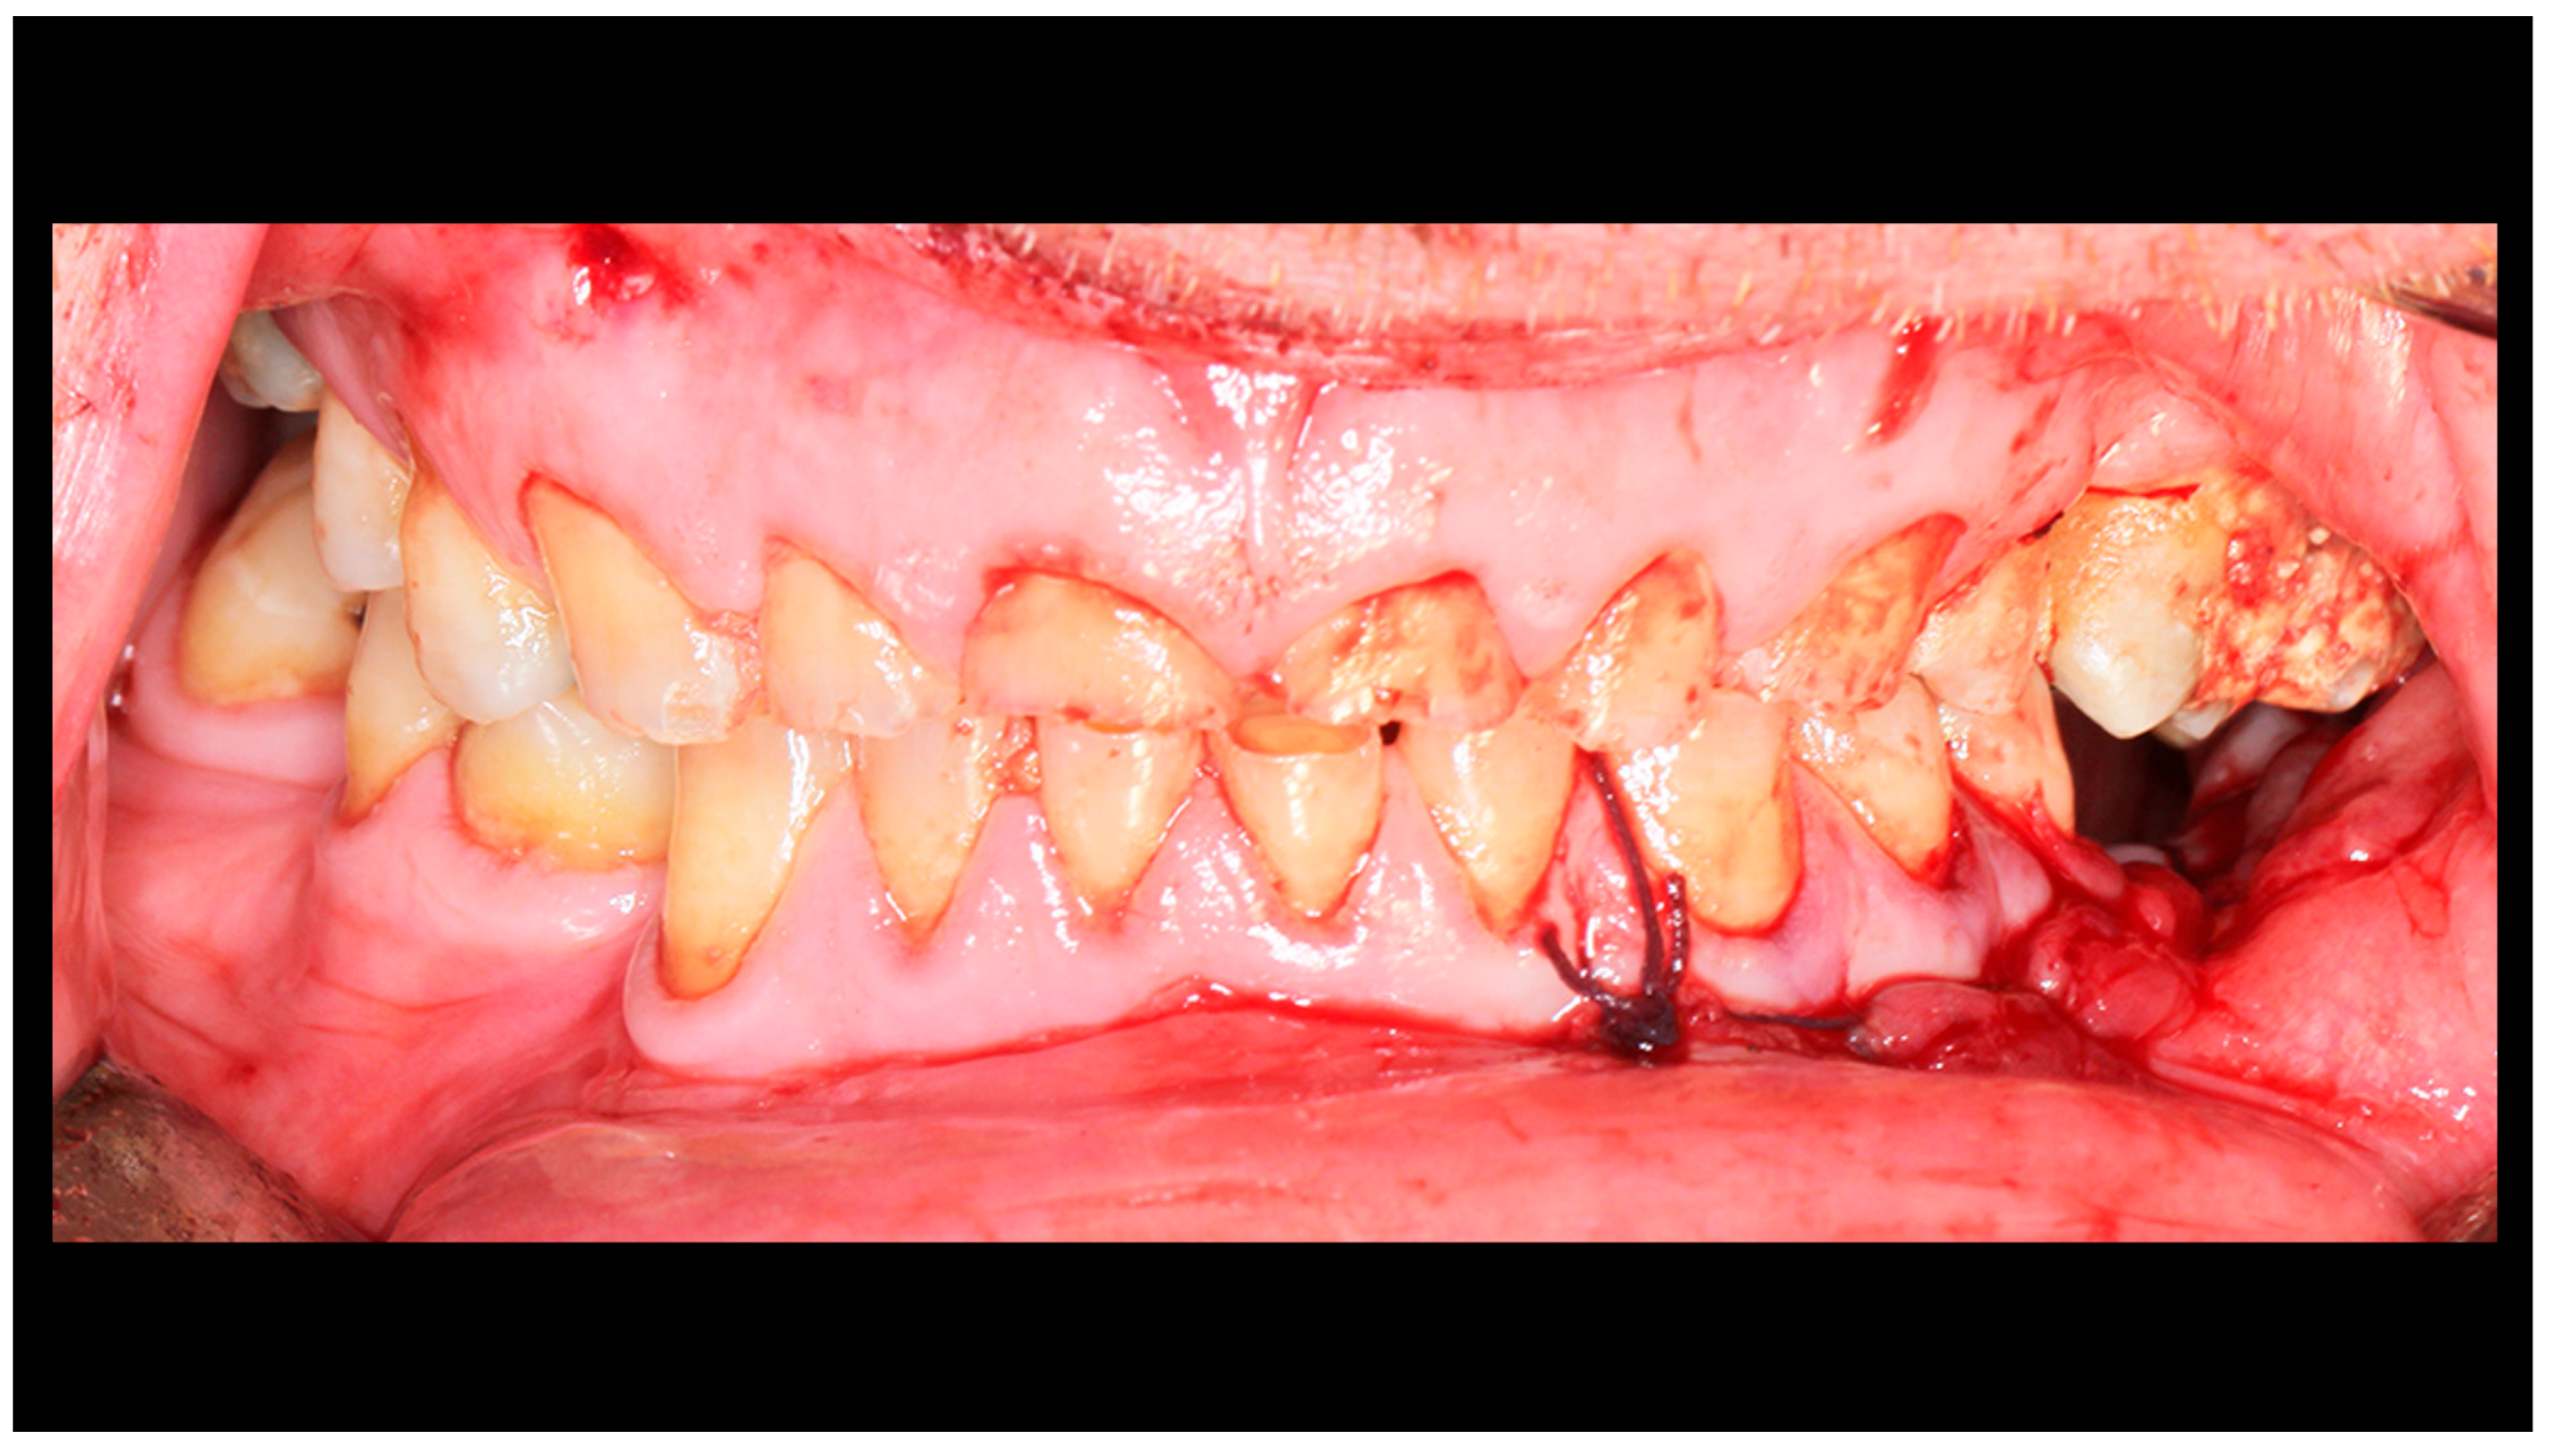

| Salivary fistula | Yes | 359 | 5.57% | 1.11% | 1.39% | 0.28% | p = 0.957 |

| No | 57.10% | 15.60% | 15.88% | 3.06% | |||

| Periauricular skin desensitization | Yes | 359 | 11.14% | 4.18% | 3.62% | 0.56% | p = 0.631 |

| No | 51.53% | 12.53% | 13.65% | 2.79% | |||